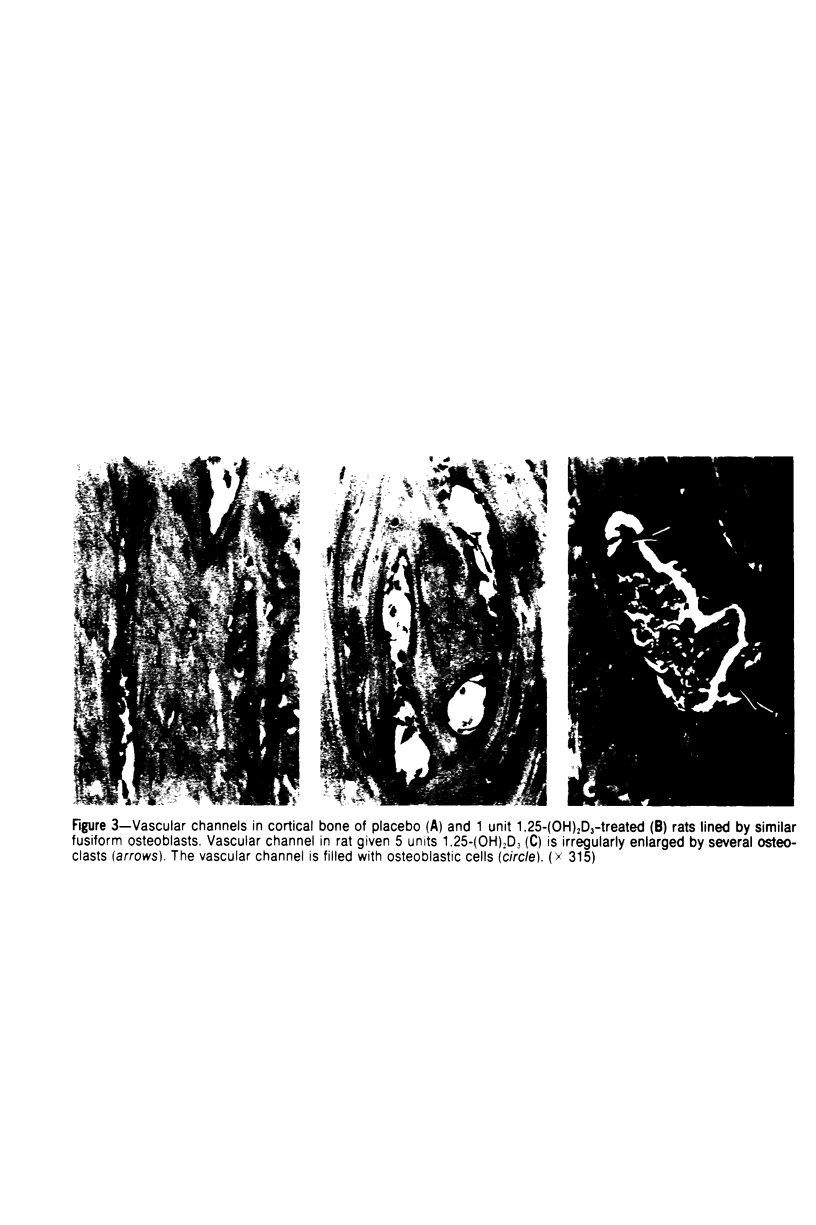

Thyroparathyroidectomized rats fed a low-calcium-normal-phosphorus diet were administered 1 or 5 units of 1,25-dihydroxyvitamin D3-(1,25-[OH]2D3) or placebo daily for 7 days. 1,25-(OH)2D3 elevated serum and urine calcium and decreased serum phosphorus. Rats given 1 unit of 1,25-(OH)2D3 had increased numbers of osteoclasts in metaphyseal trabeculae, Ultrastructurally, osteoclasts, osteoblasts, and osteocytes in rats given 1 unit of 1,25-(OH)2D3, were similar to those in rats given placebo. In rats given 5 units of 1,25-(OH)2D3, osteoclasis was markedly increased. Osteoblasts were more numerous and interpreted to be active in matrix production and mineralization. Lamellated electron-dense bodies were observed adjacent to the plasma membranes of less active osteoblasts and were interpreted to be modified matrix. Most osteocytes in rats given 5 units of 1,25-(OH)2D3 were indistinguishable from osteocytes in rats given placebo. However,the pericellular space of some osteocytes in rats given 5 units of 1,25-(OH)2D3 contained electron-dense granular deposits that were interpreted to be calcium phosphate. It is concluded that 1,25-(OH)2D3 is able to significantly elevate serum calcium independent of dietary calcium, parathyroid hormone, and calcitonin primarily by increasing ostoeclasis with minimal dependence on osteocytic osteolysis.